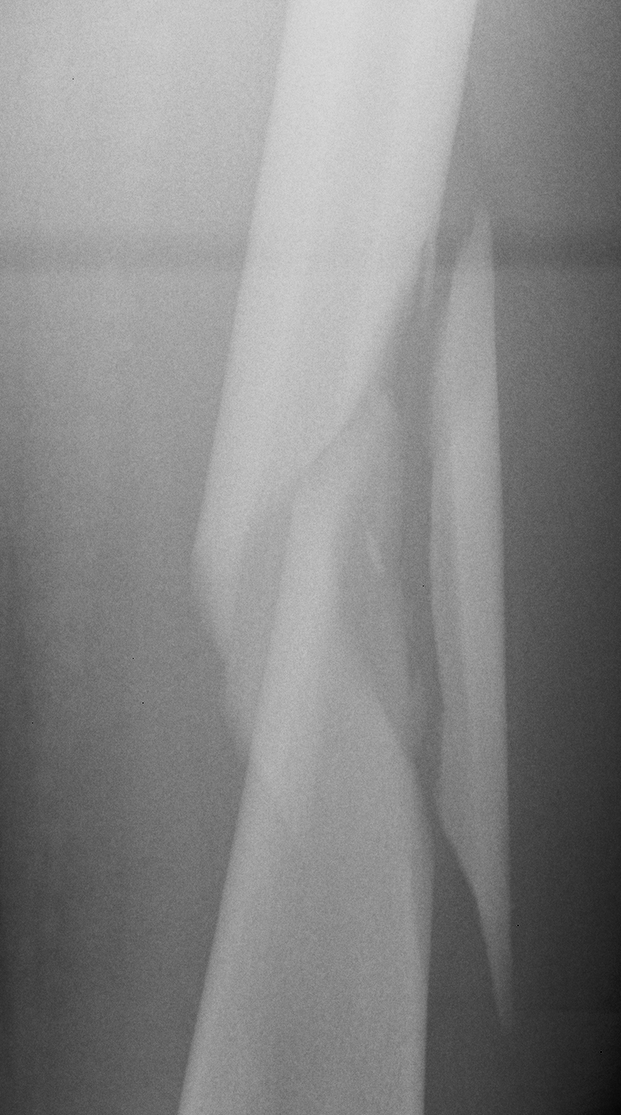

Winquist Classification

Type 1

- minimal or no comminution

Type 2

- < 50% comminution

Type 3

- 50 - 100% comminution

- inherently unstable

- needs distal locking

Type 4

- segmental comminution

- no contact or inherent stability